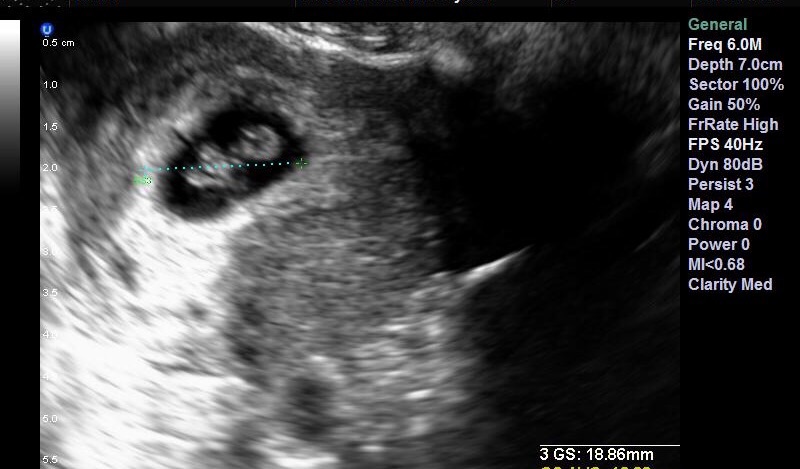

• I'm 7 weeks 1 day and am still having some light cramping. As long as it isn't severe and accompanied by bleeding it is completely normal! We saw our little one today! ❤️